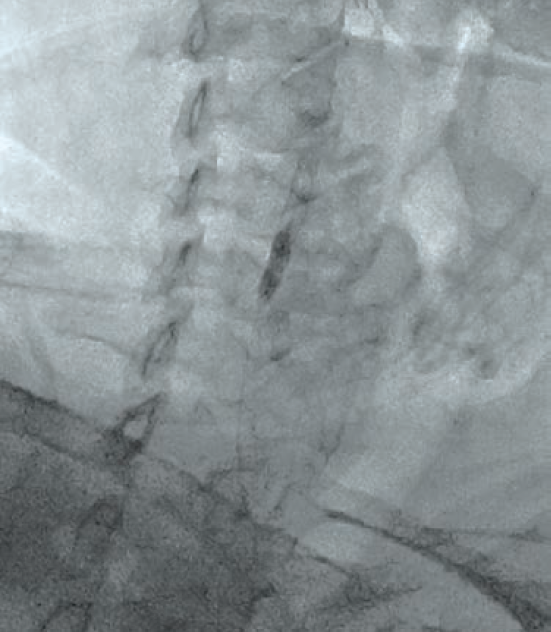

A 70-year-old hypertensive male presented with non-ST elevation myocardial infarction. Electrocardiogram showed ST depression. A complete blood count, complete blood chemistry, and PT/INR were in normal range. Lipid profile showed an LDL level of 147 mg/dl, triglycerides of 260 mg/dl, and HDL of 33 mg/dl. Coronary angiography showed triple-vessel coronary artery disease, sparing the left main stem. The patient was advised to undergo CABG surgery. During the surgical work-up, he was found to have a history of a TIA 3 months prior involving the left side of the body. Carotid Doppler showed a severe 95% ostial stenosis due to mixed plaque in the right internal carotid artery (RICA) and a mild stenosis causing 20% luminal narrowing in the left internal carotid artery. CT brain plain showed no infarction or hemorrhage. A carotid angiography and cerebral DSA showed severe stenosis at the ostium of RICA with no calcification (Figure 1). For the left ICA, both external carotid and vertebral arteries were normal. Cerebral digital subtraction angiography (DSA) showed normal intracranial circulation. A multidisciplinary approach, with a heart team including neurologists, cardiovascular surgeons, and an interventional cardiologist was adopted for this patient during the complete workup. The heart team recommended carotid revascularization prior to surgical coronary revascularization, as the patient was asymptomatic and at an intermediate risk from a coronary viewpoint. After a discussion with the patient and his family about the management options, advantages, and risks, a combined decision for CAS was made, due to its less-invasive nature as compared to CEA.

Following aseptic measures and under local anesthesia, a 7 French (Fr) right femoral access was obtained using a routine-length sheath. An .035-inch J-tip guide wire was then parked at the right common carotid artery (RCCA) using a 5 Fr Judkins right catheter, exchanged by a 7 Fr multipurpose guide. This was followed by advancement of a FilterWire EZ (Boston Scientific) across the ostial internal carotid artery stenosis, and deployed in the distal part of the extracranial ICA (Figure 2). After deployment of the FilterWire EZ, a direct stenting strategy was adopted to minimize thromboembolization. A 6 mm x 40 mm self-expanding stent was deployed at the RICA ostium (Figure 3). To our surprise, the view after stent placement showed zero flow into the distal RICA. (Figure 4) The reason appeared to be choking of the filter due to thromboembolization. The filter appeared to be overwhelmed by the volume of the debris captured. A 6 Fr Export catheter (Medtronic) was employed to suction debris from the distal ICA (Figure 5). We also administered pharmacotherapy using intra-arterial nitrate boluses and a weight-based tirofiban bolus. After these measures, there was fair flow into the distal ICA. During the period of no flow, the patient had transient hemispheric ischemic signs and an oropharyngeal airway was required, but his vitals remained stable. These symptoms rapidly resolved after establishment of ICA flow. After establishing blood flow, the proximal half of the stent that remained under-expanded was post dilated using a 4.5 mm noncompliant balloon at 12 atmospheres (Figure 6). Post dilatation, the angiographic view demonstrated good stent expansion and adequate distal flow (Figure 7). The distal protection device was then successfully removed using its retrieval sheath. The final DSA angiogram revealed excellent flow into the distal carotid (Figure 8A) and intracranial vasculature (Figure 8B), confirming no intracranial embolization. The guide was then safely removed over the .035-inch guide wire.